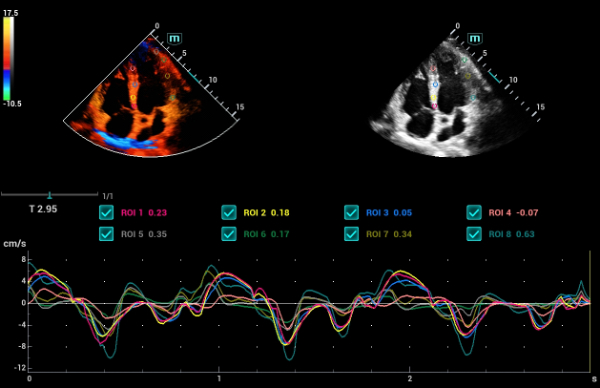

Independientemente de si lleva a cabo su rutina en hospitales o clĂnicas, o si estĂĄ perfeccionando sus habilidades en aplicaciones de diagnĂłstico por imĂĄgenes generales, atenciĂłn de la salud de la mujer o especialidades cardiovasculares, esta serie dispone de herramientas muy potentes para que se mantenga a la vanguardia.

GalerĂa de imĂĄgenes